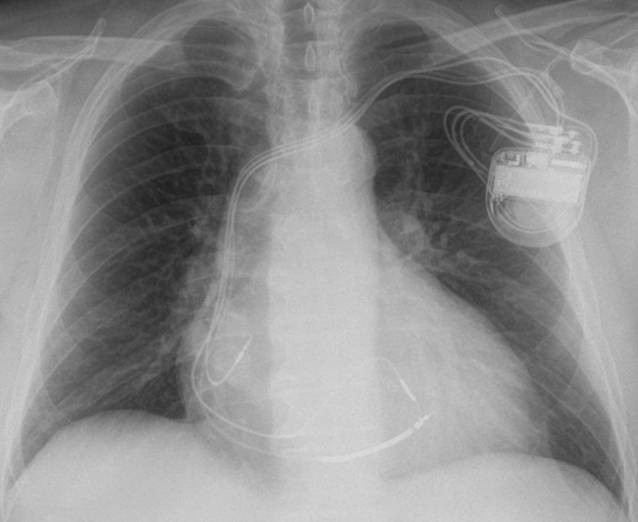

Dekompensierte Herzinsuffizienz mit Pleuraergüssen infolge AV-Block III mit Kammerfrequenzenzen um 32/min (oben; Thorax pa); Rekompensation nach Herzschrittmacher-Implantation (2-Kammer-Schrittmacher mit je einer bipolaren Elektrode im rechten Vorhof und im rechten Ventrikel; Thorax pa) |